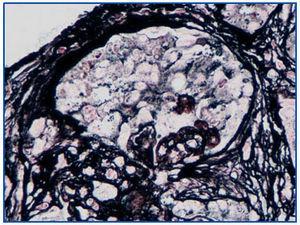

Se realizó biopsia renal en la se mostraban 9 glomérulos, 5 de ellos completamente esclerosados y 4 presentaban lesiones de esclerosis segmentaria; en estos últimos, destacaba una hiperplasia e hipertrofia del epitelio visceral (pseudosemilunas) (Figura 1), en ocasiones, vacuolizado (PAS +), ocupando el espacio de Bowman pero con epitelio parietal no afecto. Los capilares de estos glomérulos presentaban áreas de colapso y oclusión luminal (Figura 2). El intersticio era edematoso, con moderada infiltración inflamatoria mixta y túbulos muy alterados, con dilatación de luces y epitelio, a veces, necrótico o degenerado y células desprendidas en su luz (Figura 3). El componente vascular no mostraba lesiones.

Figura 3. Necrosis y dilatación tubular. HE 20x.